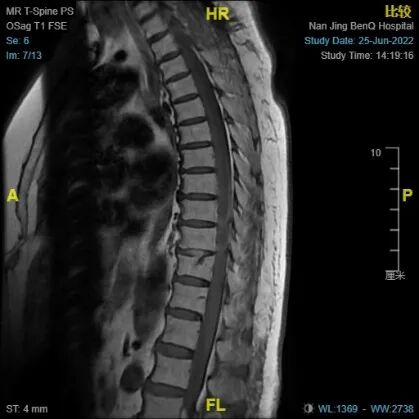

术后MRI

该手术在全麻下进行,采用显微镜下微创手术切除了胸椎管内肿物。术后,朱阿婆直接进入普通病房进一步治疗,在术后第1天精神良好,右侧下肢肌力恢复至1级,左下肢肌力也有了相应的改善。在术后第3天双下肢肌力恢复至3级,双脚已经能够独立抬离床面,并且双下肢的感觉障碍也在改善。在术后1周,朱阿婆已经能够下床站立和短距离行走,同时在进行科学的抗尿路感染治疗和评估之后,导尿管也被拔除。随病情改变的还有朱阿婆的心情和笑容。术后病理提示为良性的脊膜瘤。